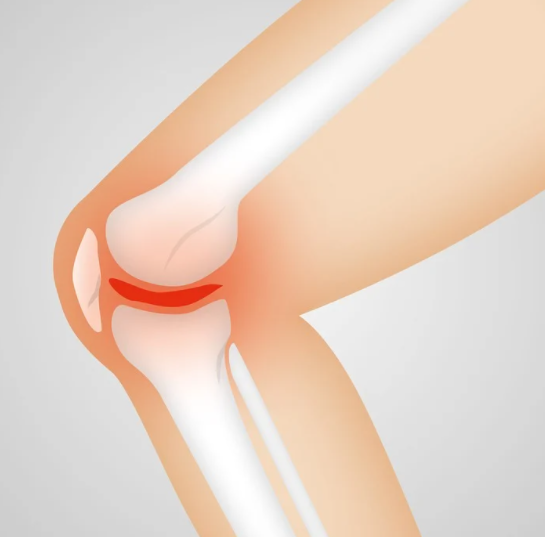

이유3. 골다공증

아마 골다공증은 가장 흔하게 겪는 무릎이 시린 이유 중 하나일 것이다. 골다공증은 보통 50대 이상의 중장년의 여성들에게 자주 발생하는 질환으로 매년 골다공증을 겪는 환자는 많아지고 있다고 한다. 50대 이상이 골다공증을 겪는 비율이 90%라고 하니 무릎이 시린 이유 중 가장 대표적인 이유가 아닐까 생각한다.

골다공증이 중년여성에게서 많이 생기는 이유는 바로 완경에 의한 여성호르몬 수치의 감소로 뼈가 약해지기 때문이다.

무릎이 시린 이유인 골다공증은 왜 일어나는걸까?

우리 몸을 구성하는 뼈는 한 번 생기면 평생 사라지지 않는것이 아니라 다시 만들어지고 사라지고 하는 과정을 반복한다. 30대만 해도 사라지는 뼈보다는 생성되는 뼈가 더 많다. 하지만 30대 이후 40대를 지나 50대가 되면 사라지는 뼈가 훨씬 더 많게 되는 것이다.

그래서 골밀도가 저하되고 골다공증이 시작된다고 할 수 있다.

골다공증이 남성보다 여성에게 많이 일어나는 이유는 여성이 출산과 완경을 겪기 때문이다.

무릎이 시린 이유가 골다공증이라면 비단 무릎뿐만 아니라 엉덩이나 허리가 함께 아프면서 다리를 저는 증상이 수반될 가능성이 있다.

골다공증으로 인한 골절이 발생했다면 적극적인 치료를 해야한다는 것을 명심해야 한다.

골다공증으로 인한 골절 환자 중에서 40%만 약물치료를 받을 뿐 그 중 60%의 환자들은 치료를 중단하는 경우가 많다. 치료를 중간에 멈추게되면 골소실이 빠르게 일어나 다른부위에 재골절이 발생할 수 있다는 위험성을 인지하기를 바란다.

평소에 무릎이 계속 시큰거리고 골다공증이 의심된다면 빠르게 치료에 임하는 것도 좋은 방법이 될 거라고 생각한다.